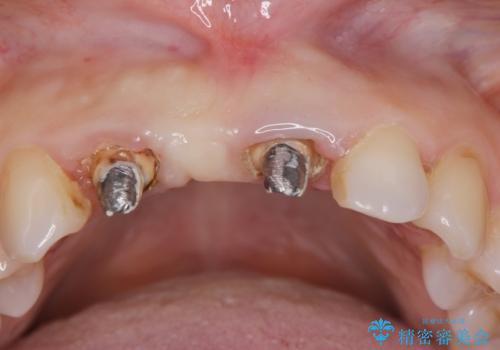

- 前歯のブリッジがすぐに外れる、歯ぐきが腫れている、見た目を良くしたい、と希望され来院されました。

現在装着されているブリッジを除去したところ、歯ぐきよりも上に存在する歯質(縁上歯質)が少なく、土台の形態の悪さや不適合などさまざまな問題があります。